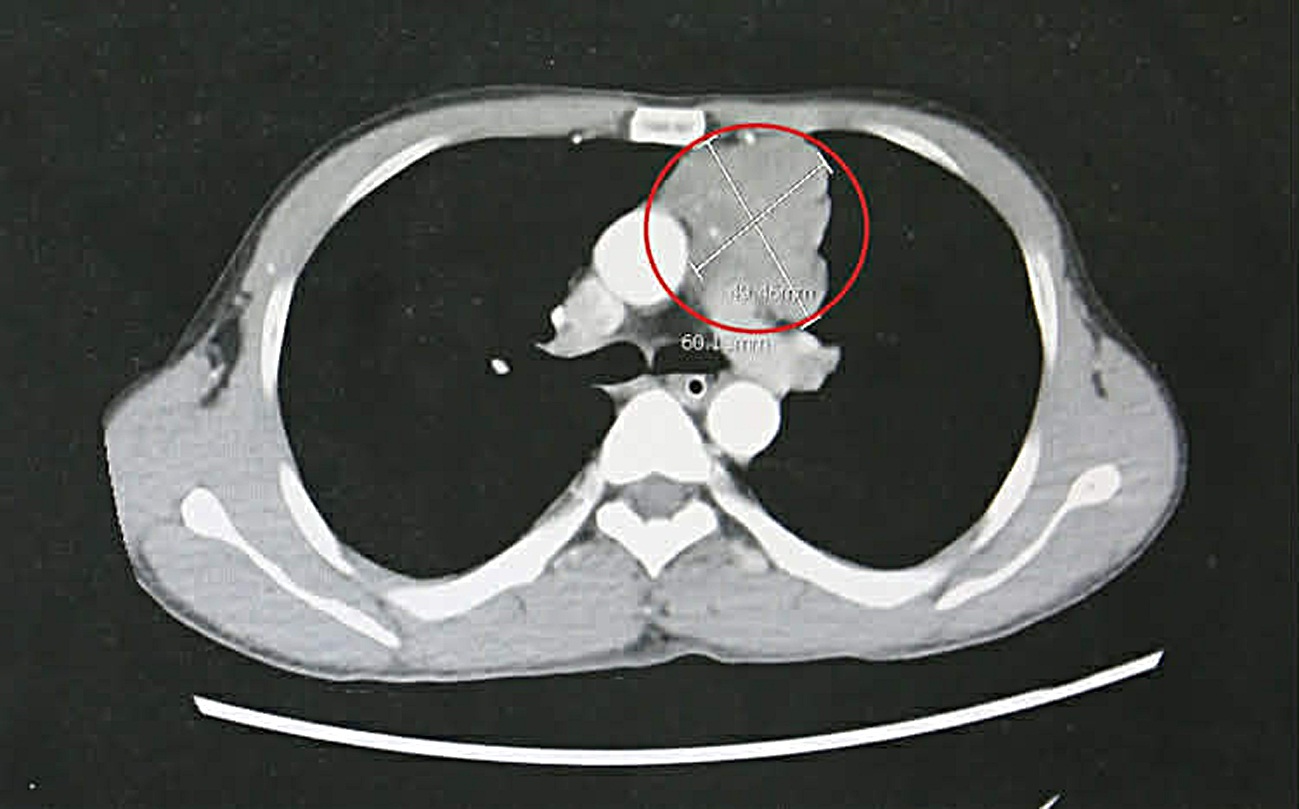

Qua thăm khám lâm sàng, cơ lực chi chỉ còn 3/5, phản xạ kém, cơ lực cổ yếu, cơ hô hấp suy giảm. Kết quả chụp cắt lớp vi tính lồng ngực phát hiện khối u trung thất trước kích thước lớn khoảng 4 x 6cm, xâm lấn thần kinh hoành, bên trong có vôi hóa.

Bệnh nhân được chẩn đoán nhược cơ nặng do khối u tuyến ức và chỉ định phẫu thuật cắt toàn bộ tuyến ức giúp loại bỏ nguyên nhân gây nhược cơ.

Khối u tuyến ức kích thước lớn của bệnh nhân gây nhược cơ – Ảnh BVCC